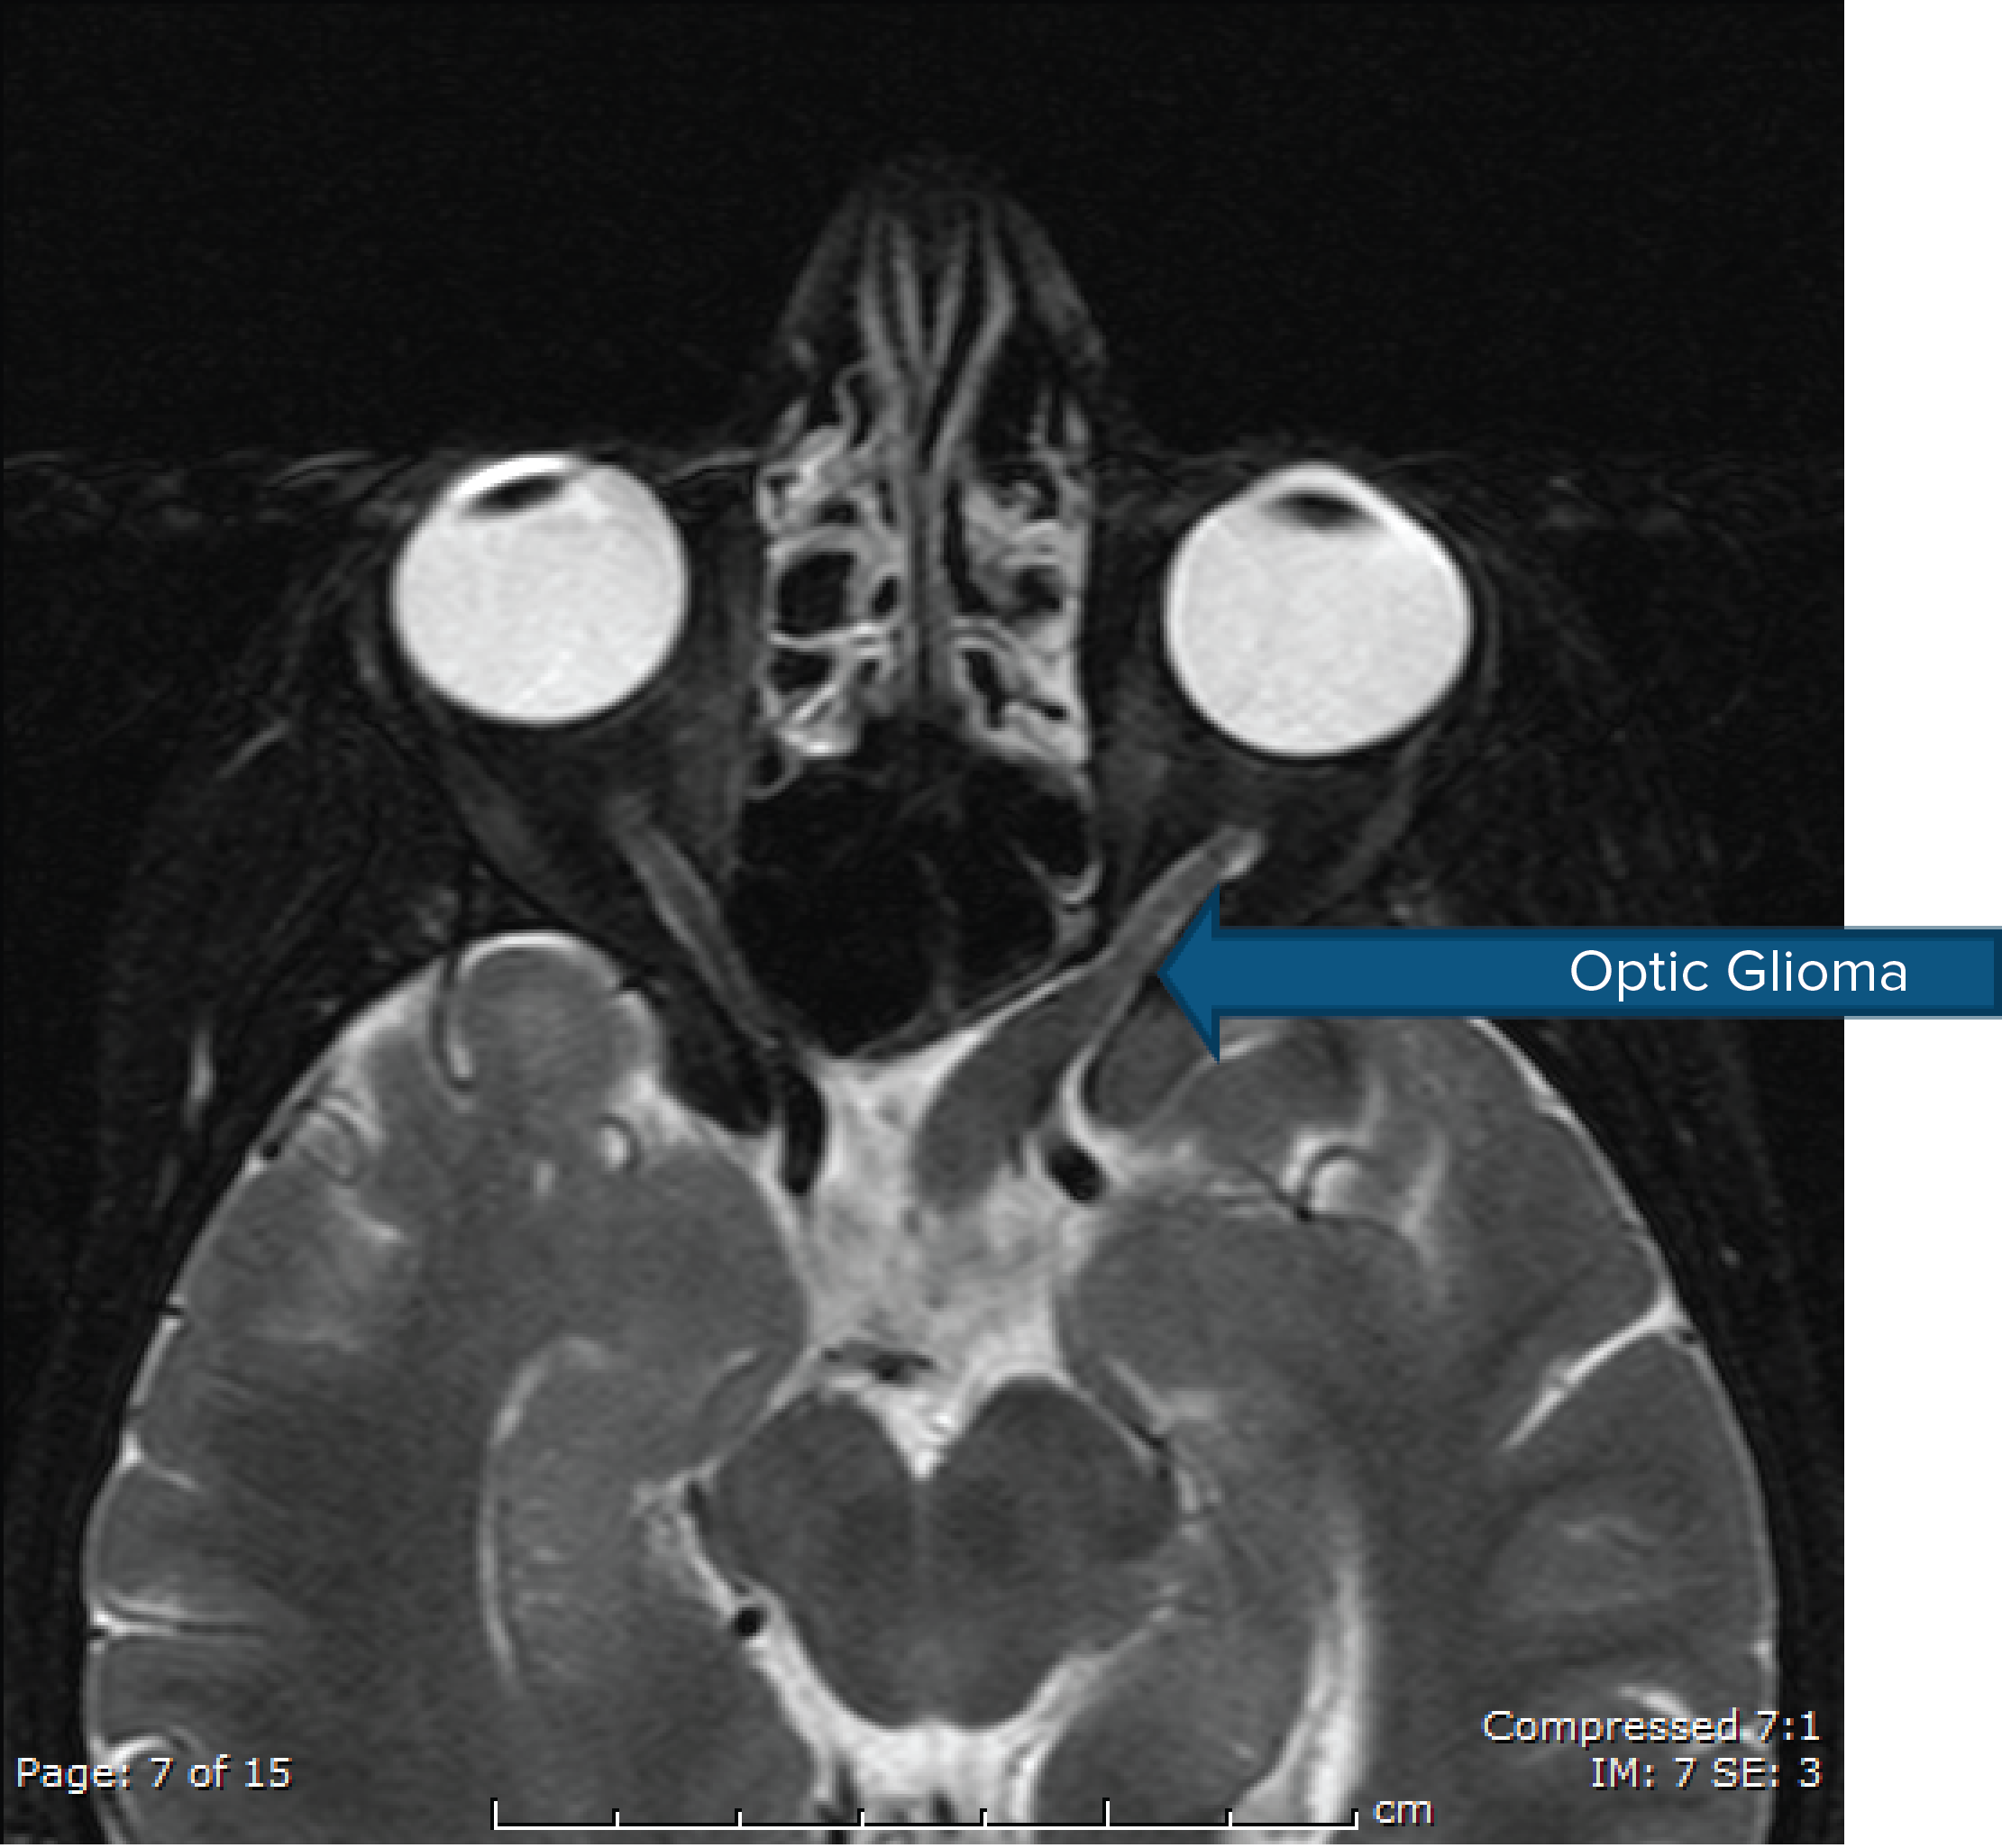

Optic Glioma

6. Optic nerve glioma

Common clinical findings on exam include café au lait spots, neurofibromas, Lisch nodules, and optic gliomas. MRI brain imaging may show T2 signal change in the subcortical region in addition to tumors, often call neurofibroma bright objects (NBOs).

Other presenting symptoms may include cognitive dysfunction, pain in specific nerve distribution (usually due to presence of neurofibroma), seizures, changes in vision that may be related to optic gliomas, seizures from intracranial tumors, stenosis of major intracranial arteries leading to Moyamoya phenomenon, headaches, and progressive neurologic deficits.